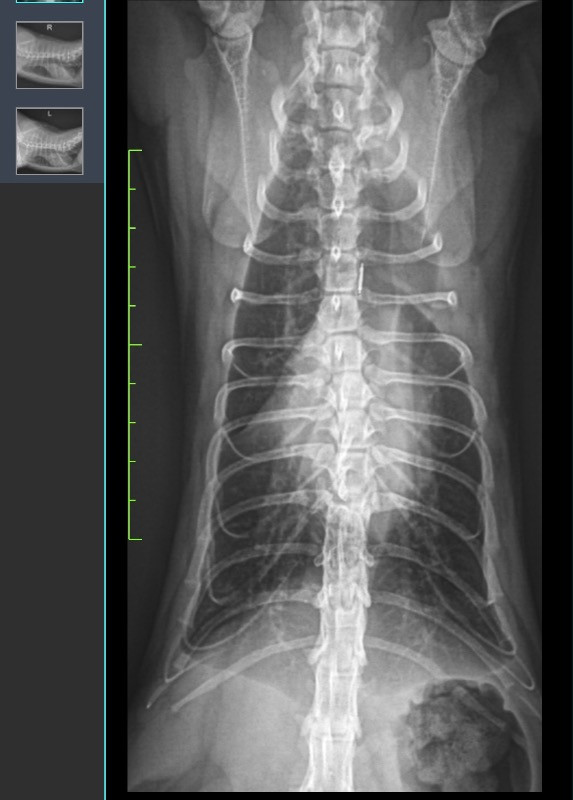

Anni安妮???????? 2026-02-13 貓咪10月大想詢問還有沒有機會不要透過開刀之外的方式矯正背部脊椎凹陷的問題 目前是透過骨科專科穿矯正馬甲將下腹骨骼拉開讓胸腔部分擴大 減少肺及心臟壓迫 0 分享–– 我也要提問